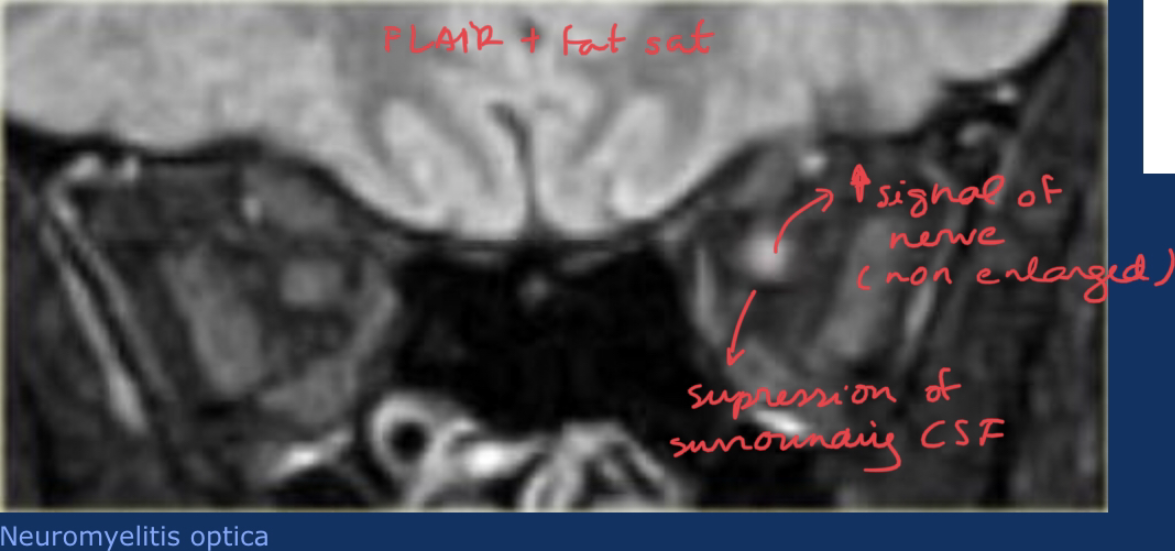

What you expect to see in MRI, in Neuromyelitis optic (Devic syndrome)?